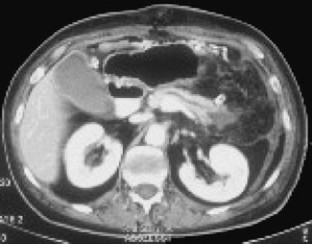

Bei einer 63-jährigen Patientin mit o. g. Risikofaktoren, einem Pancreas divisum und vermeintlichem zystischen Pankreasschwanztumor, der sich als Pseudozyste bei einer Pankreatitis herausstellte, erfolgte eine 2-jährige Behandlung rezidivierender Pankreatitisschübe. Erst bei der Behandlung eines komplizierenden Leberabszesses fiel in einer CT eine malignitätssuspekte, zum Aufstau des Pankreashauptganges führende Pankreaskopfraumforderung auf. Retrospektiv waren Gangveränderungen schon auf Voraufnahmen sichtbar. Die partielle Duodenopankreatektomie bestätigte das Pankreaskopfkarzinom.

A 63-year-old female patient with suspected cystadenocarcinoma of the pancreas tail, which was resolved as a pancreatic pseudocyst, was treated for recurrent pancreatitis for 2 years. A tumor in the pancreas head was only detected on a follow-up CT after resection of a complicating liver abscess. In retrospect, progressive pancreatic duct anomalies were visible on previous scans. Partial duodenopancreatectomy confirmed the presence of a pancreas head carcinoma.